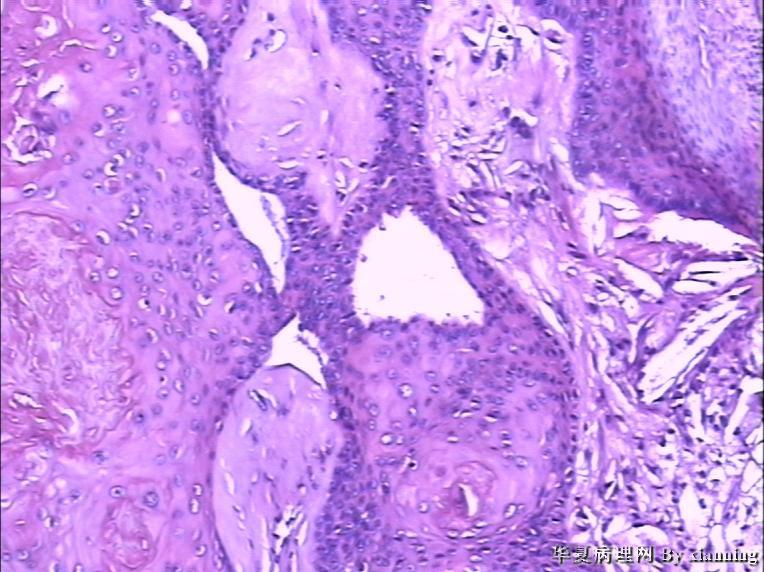

女 50岁 头皮下肿块

巨检:灰白色不规则结节0.9*0.7*0.4cm3,切面灰白色实性质地中等

名称:图1

描述:36580003